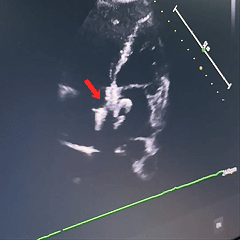

术后第二天随访

房间隔可见封堵器回声,位置固定,形态良好。房水平未见残余分流信号。

术后即刻超声检查显示封堵器位置正确、形态良好、夹持稳定,无残余分流。术后第1天和第2天的随访超声进一步显示房间隔可见封堵器回声,位置固定,形态良好,且房水平未见残余分流信号。